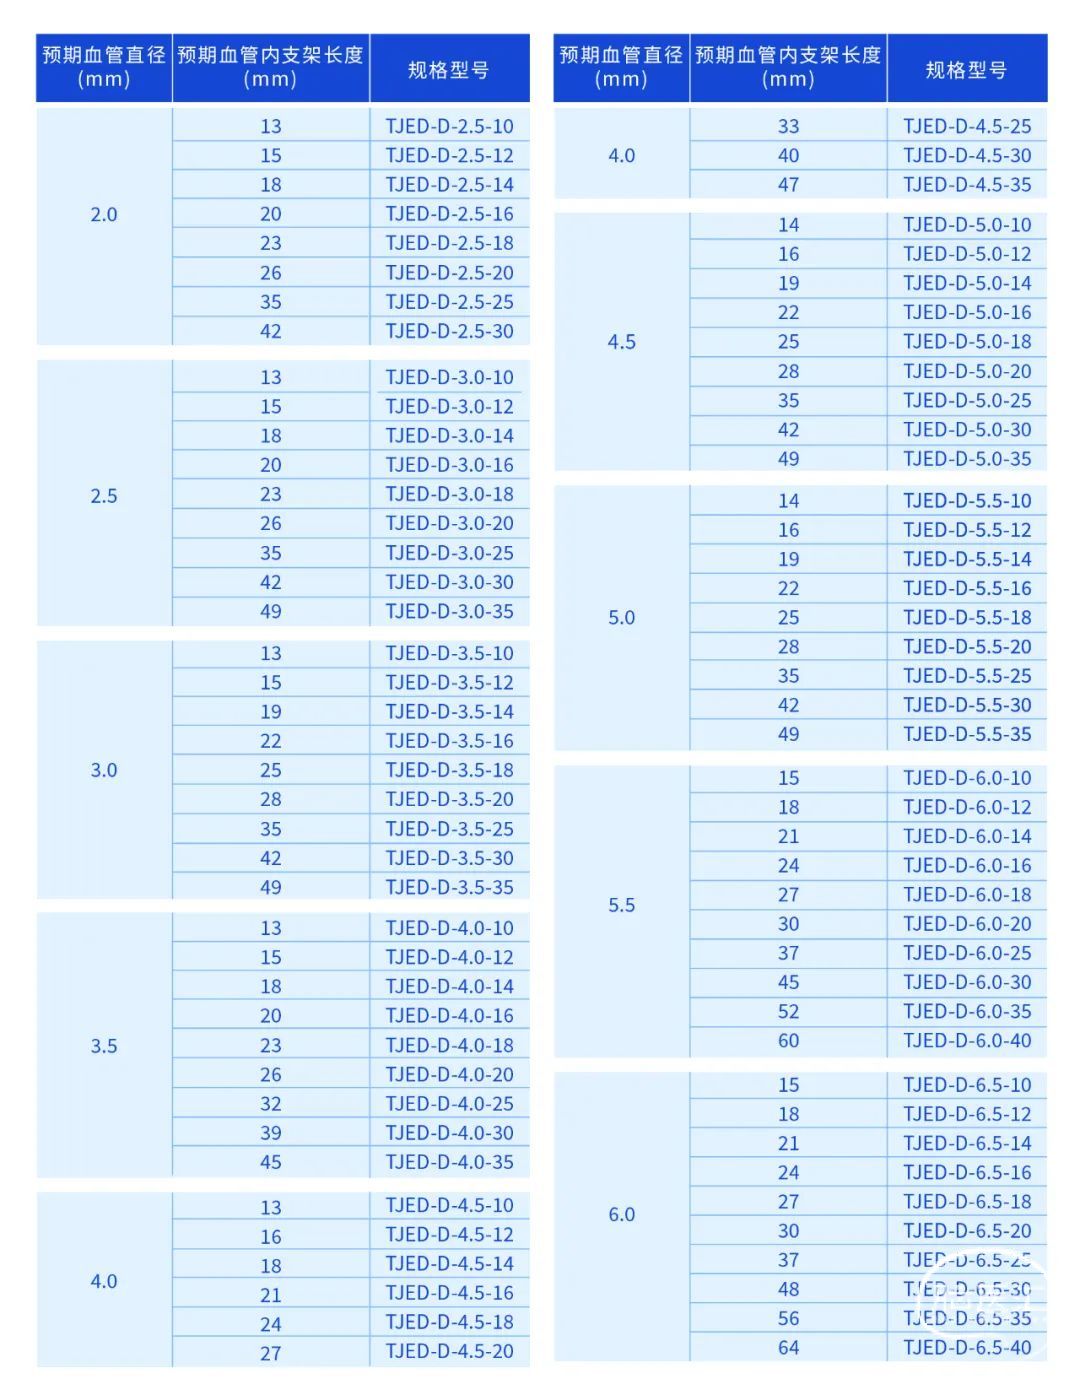

Nuva®血流导向密网支架提供9种外径选择,规格型号多达82种,适应载瘤血管直径2.0~6.0mm,为患者和医生提供全方位的动脉瘤治疗方案。